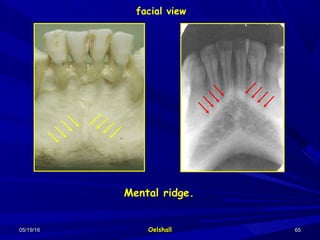

Mental ridge:Mental ridge: It is a bony prominence found on the labialIt is a bony prominence found on the labial

aspect of the mandible near its inferior border and extendedaspect of the mandible near its inferior border and extended

from the premolar region to the symphysis area on which itfrom the premolar region to the symphysis area on which it

takes an upward turn as it approach it. It appears as atakes an upward turn as it approach it. It appears as a

radiopaque line below the apices of anterior teeth.radiopaque line below the apices of anterior teeth.

Mental ridge.

facial view